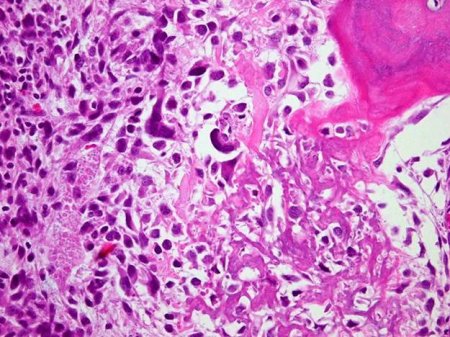

Histological examination of biopsy sample confirms a diagnosis of osteosarcoma.[23][Figure caption and citation for the preceding image starts]: Osteoblastic osteosarcoma; lace-like osteoid in a highly pleomorphic sarcomatous stromaPersonal collections of Dr Michael J. Klein and Dr Luminita Rezeanu [Citation ends].

highly pleomorphic spindle cell neoplasm producing osteoid or immature bone; osteoid typically has a lace-like appearance; neoplastic cells and osteoid show a permeative growth pattern with invasion of the native bone trabeculae; neoplastic cartilage can also be produced by the tumour cells; mitotic activity is high and composed of atypical mitotic figures